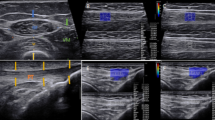

Electromyography

Surface electromyography signal (sEMG) from the right quadriceps was recorded throughout the 1STS (FreeEMG300, BTS Bioengineering, Milan, Italy) with a bioelectric signal amplifier, wireless transmission, and bipolar electrodes. The sEMG signal was high-pass-filtered (1 kHz) and preamplified near the recording electrodes. Electrodes were placed on the muscle bellies, longitudinally with respect to the underlying muscle fibers arrangement and were located according to the surface electromyography for the non-invasive assessment of muscles (SENIAM) recommendations25. Before placing the electrodes, the electrical impedance of the skin was reduced by shaving the hair and by cleaning the skin with alcohol. An electrogoniometer (FreeEMG300, BTS Bioengineering, Milan, Italy) was placed on the participant’s left leg to record and dissociate the sitting and standing phases during the 1STS.

All sEMG signals were analysed using custom software written in MATLAB R2018a (The Math Works Inc., Natick, Massachusetts, United States). The signals were digitally filtered off-line with a zero lag fourth order Butterworth filter (band-pass 20–450 Hz) and amplitude analysis was performed using a root mean square-based envelope (root mean square of a non-overlapping 20 ms rectangular window). The signals were cut and time-normalized for each sit-to-stand (one cycle) using the electrogoniometer signals during 1STS. Mean of sEMG envelopes was calculated for each cycle. Frequency analysis was performed on digitally filtered data prior to root mean square envelope and time normalization steps. Power spectral median frequency was calculated for each cycle and time duration of each cycle was extracted.

Changes in quadriceps (a) median frequency and (b) root mean square during the 1-min sit-to-stand (1STS), expressed in % baseline value in people with COPD (full circles) and healthy controls (open circles). Results are presented as mean ± SEM. *p < 0.01, 60 s compared to 15 s. The p values report the interaction group × time during the 1STS.

Quadriceps sEMG was not recorded for three people with COPD and four healthy controls because of technical problems. In people with COPD, there was a fall in quadriceps median frequency during 1STS (6.9% ± 2.4%, p < 0.01) (Fig. 4), while in healthy controls the median frequency of the muscle remained stable during the test. Despite these within-group differences, the overall pattern of changes in median frequency did not differ between COPD and healthy controls (p = 0.913) (Fig. 4a). Root mean square of the quadriceps decreased during 1STS in people with COPD (p < 0.01), while it remained stable in healthy controls (Fig. 4b). The overall pattern of changes in root mean square was statistically different between people with COPD and healthy controls (p = 0.003) (Fig. 4b).